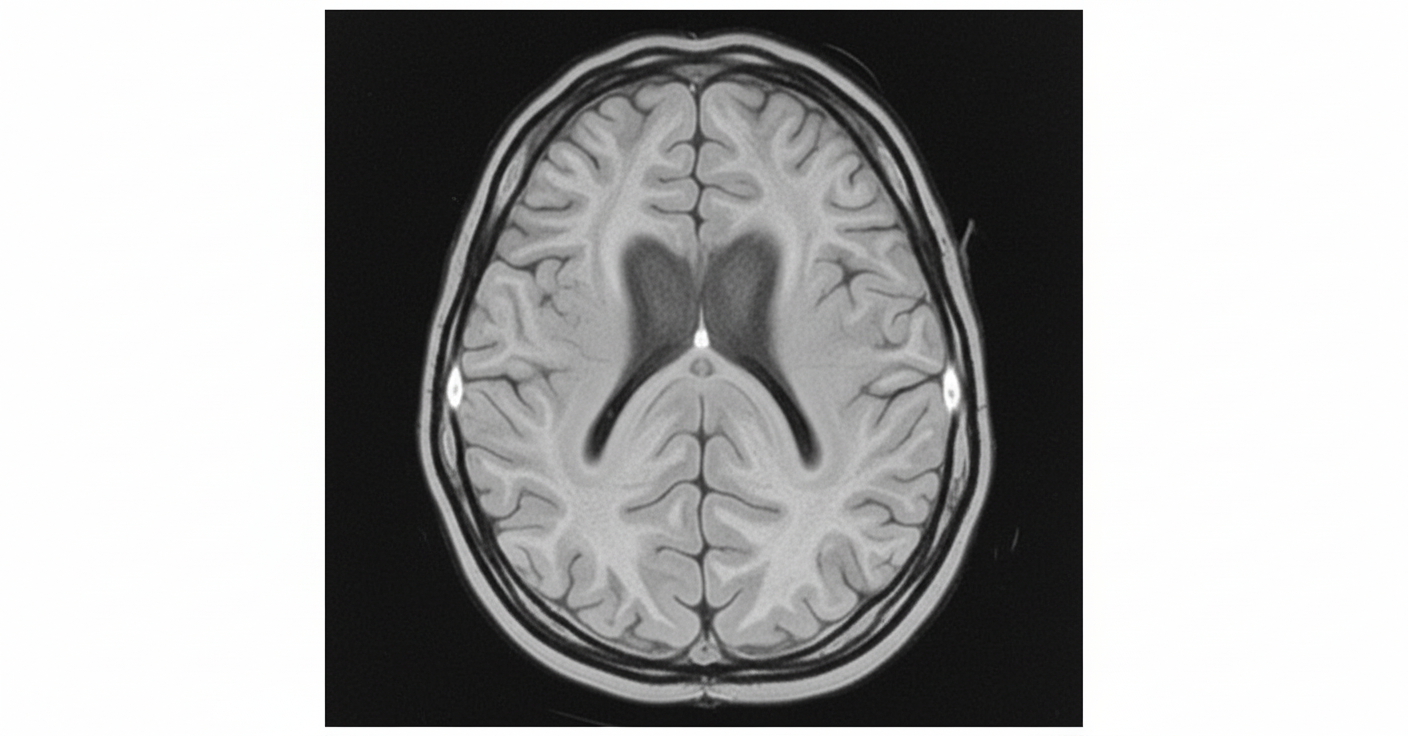

The MRI image shows a smooth brain surface with absence of normal gyri and sulci. What is the diagnosis?

Explanation: ***Lissencephaly*** - The image clearly displays a **smooth brain surface** with a notable **absence of normal gyri and sulci** (brain folds), characteristic of lissencephaly - This "smooth brain" appearance is pathognomonic for **lissencephaly**, a severe neuronal migration disorder resulting from abnormal neuronal migration during fetal development (typically 12-16 weeks gestation) - Associated with severe developmental delay, seizures, and intellectual disability - Caused by mutations in genes like LIS1, DCX, and TUBA1A *Incorrect: Schizencephaly* - Characterized by **clefts or splits** extending from the ventricles to the cortical surface, lined by gray matter - Would show a clear **CSF-filled cleft**, not a smooth brain surface *Incorrect: Polymicrogyria* - Features **excessive small gyri** with abnormal cortical layering - Brain surface appears bumpy or irregular, not smooth *Incorrect: Pachygyria* - Shows **broad, thick gyri** with shallow sulci - Still has visible gyri and sulci, unlike the completely smooth appearance of lissencephaly

Explanation: ***Lissencephaly*** - The image shows a **smooth brain surface** with **absent or reduced gyri and sulci**, which is characteristic of lissencephaly. - This condition is often associated with **developmental delay** and **epilepsy**, consistent with the child's presentation. *Subdural hemorrhage* - A subdural hemorrhage would appear as a **crescent-shaped collection of blood** between the dura mater and arachnoid mater. - The image does not demonstrate any such blood collection. *Arnold-Chiari malformation* - Arnold-Chiari malformation involves the downward displacement of the **cerebellar tonsils** into the foramen magnum. - While it can cause neurological symptoms, the primary finding in the image is a smooth cerebral cortex, not cerebellar displacement. *Schizencephaly* - Schizencephaly is characterized by **clefts or slits in the cerebral hemispheres** that extend from the pial surface to the ventricles. - The image shows a smooth brain surface rather than distinct full-thickness clefts.